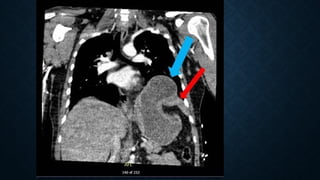

Tension haemopneumothorax. Axial contrast-

enhanced CT at mediastinal window shows a

right tension haemopneumothorax with

heterogeneous increased density due to

presence of blood clots and a significant shift

of the mediastinum contralaterally.